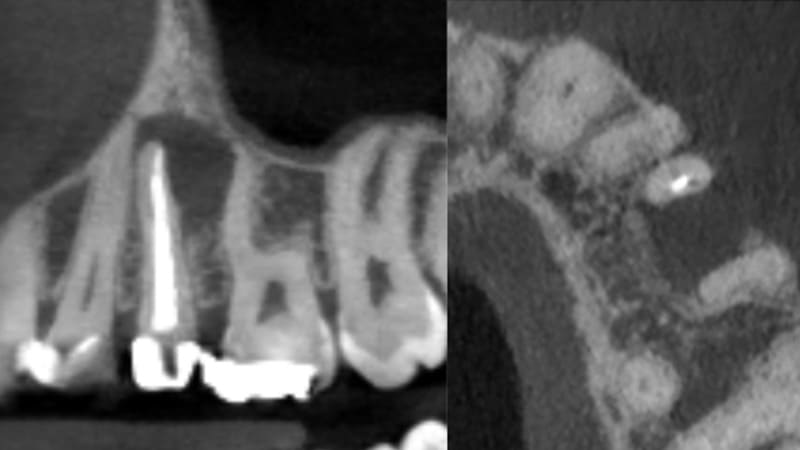

症例②:右上の奥歯がたまにうずく

| 治療科目 | 根管治療、セラミッククラウン |

|---|---|

| 主訴 | 右上の奥歯がたまにうずく |

| 治療期間 | 3ヶ月 |

| 治療費 | セラミッククラウン 121,000円 |

| 治療内容 | 奥歯、銀歯を除去しマイクロスコープを使い根管内洗浄、根管充填した。仮歯で1ヶ月経過観察後症状消失したため最終補綴(ジルコニアクラウン)装着。 |

| 治療のリスク | 噛み合わせが強い場合歯根破折の可能性あります。 まれに再発する可能性があります。 その場合外科的歯内治療をするか、抜歯を検討します。 |